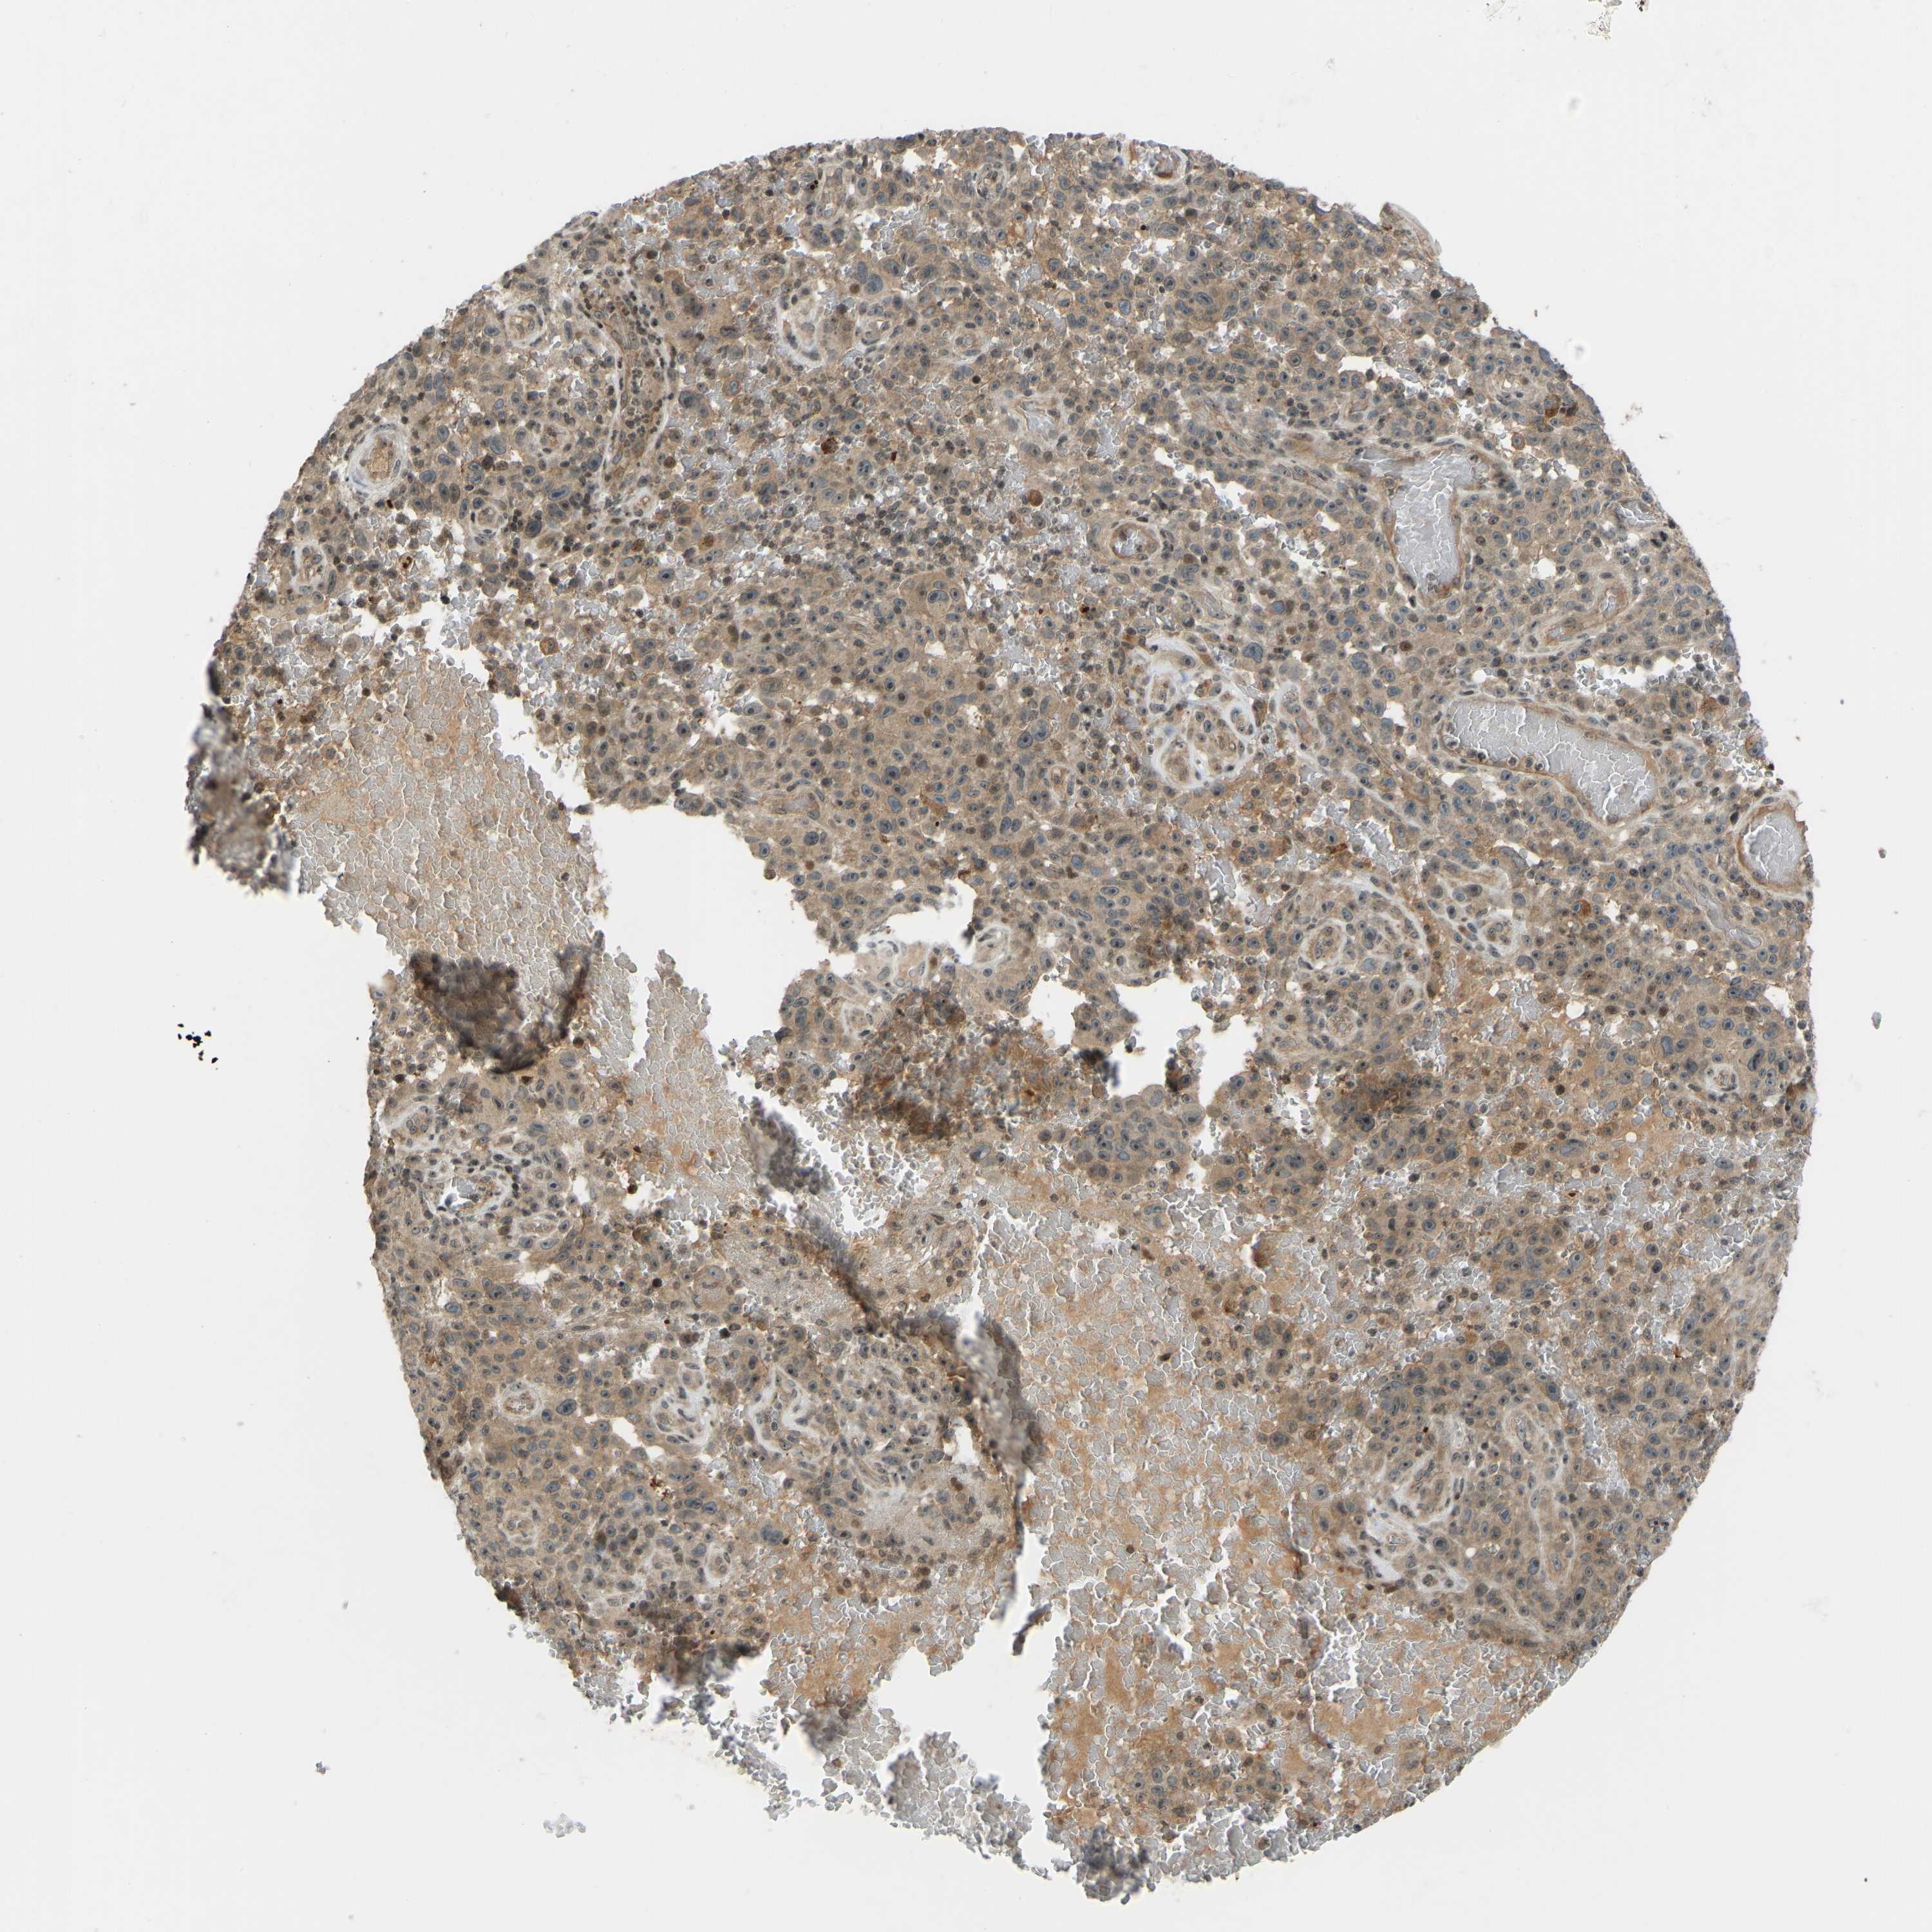

MELANOMA - Protein expressioni

A mouse-over function shows sample information and annotation data. Click on an image to view it in a full screen mode. Samples can be filtered based on level of antibody staining by selecting one or several of the following categories: high, medium, low and not detected. The assay and annotation is described here.

Note that samples used for immunohistochemistry by the Human Protein Atlas do not correspond to samples in the TCGA dataset.

Antibody stainingi

Antibody staining in the annotated cell types in the current human tissue is reported as not detected, low, medium, or high, based on conventional immunohistochemistry profiling in selected tissues. This score is based on the combination of the staining intensity and fraction of stained cells.

Each image is clickable and will lead to virtual microscopy that enables deeper exploration of all samples and also displays staining intensity scores, fraction scores and subcellular localization as well as patient and tissue information for each sample.

Antibody HPA018035

Staining

High

Medium

Low

Not detected

Intensity

Strong

Moderate

Weak

Negative

Quantity

>75%

75%-25%

<25%

None

Location

Nuclear

Cytoplasmic/membranous

Cytoplasmic/membranous,nuclear

Malignant melanoma, NOS

Malignant melanoma, Metastatic site